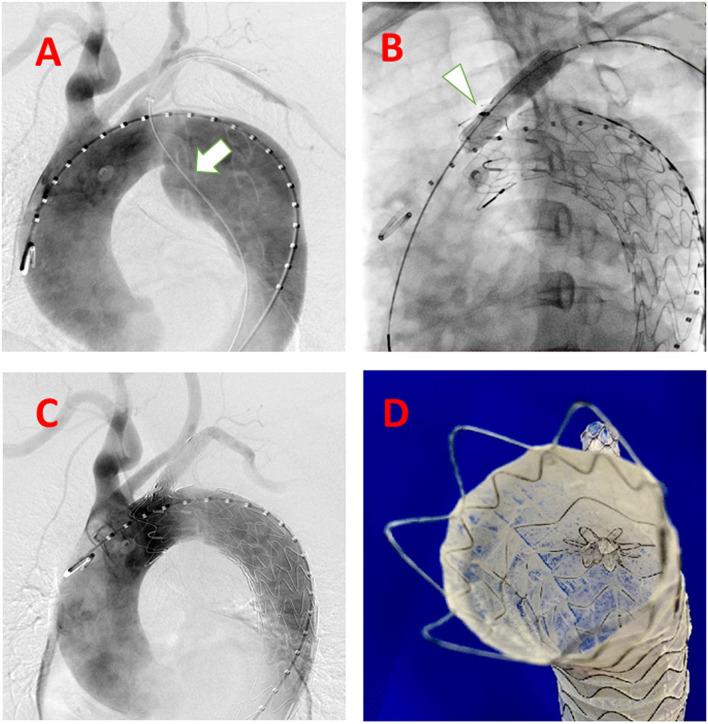

DESCRIPTION

The gutter-free stent-graft has a nickel-titanium self-expanding skeleton, double polytetrafluoroethylene coating, and an outer-skirt fabric structure (named C-skirt endograft). The outer skirt fabric prevents endoleak from the gutter around the stent graft fenestration. Further, the skirt structure right under the fenestration in the aortic stent graft can function as a fixation of the side-branch artery endograft. These designs have the following advantages, such as: 1) prevention of endoleak; and 2) fixation tightly between the branch and aorta endograft pieces.

EVALUATION

A patient who was diagnosed with an aortic arch aneurysm, combined with localized dissection, has successfully implanted the aortic stent graft and C-skirt endograft for the left subclavian artery. The 6-month follow-up result of the C-skirt in situ fenestration TEVAR is satisfactory without obvious endoleak.

评估

一名被诊断为主动脉弓瘤合并局限性夹层的患者成功植入了主动脉支架型人工血管及用于左锁骨下动脉的C裙边腔内移植物。C裙边原位开窗TEVAR的6个月随访结果令人满意,无明显内漏。